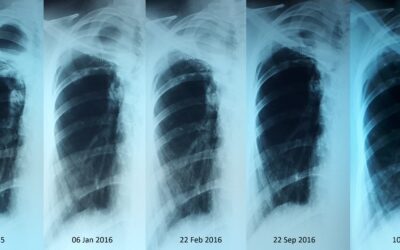

Трахеобронхиальное стентирование, рубцовый стеноз левого главного бронха.

Трахеобронхиальное стентирование, рубцовый стеноз левого главного бронха.Пациент 49 летний мужчина. В 2007 году он лечился по поводу туберкулеза легких. В 2015 году - релапс. В течении многих лет у пациента одышка, возростаюшаяся недостаточность дыхания, из за чего...